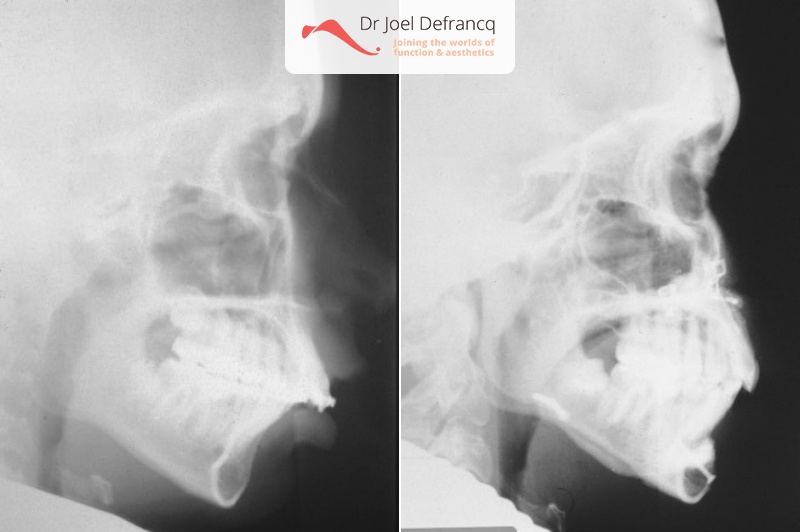

Darsa: Bovenkaak te groot en te veel naar voor

Kaakchirurgie

- Verlenging onderkaak (BSSO)

- Naar achter plaatsen bovenkaak (Le Fort I)

- Kinchirurgie

- Bovenkaak werd tevens versmald via midline split